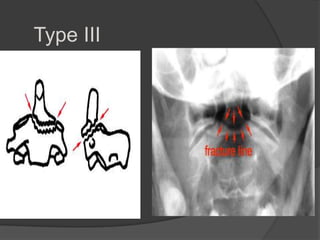

Type III (7%)

 displaced C2

 C2-3 Bilateral interfacet dislocation

 Severe instability

Classification

Type III: Fracture through the

body of the axis and

sometimes facets.

Can be unstable, but has a

better prognosis than type II

due to better healing of the

fracture which runs through

the metaphyseal body of C-2